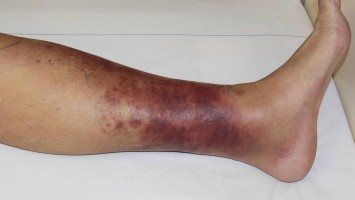

Häufige Haut- und Weichgewebeinfektionen – aktuelle Leitlinie

Abszesse, Erysipele oder unkomplizierte Phlegmonen gehören zu den häufigsten Infektionen in dermatologischen Praxen. Diese Übersicht auf Basis der neuen Leitlinie soll helfen, Weichgewebeinfektionen gezielt antibiotisch zu behandeln und Resistenzen zu vermeiden.

Titelbild Kongress Kompakt EULAR 2025/© Hintergrundbild: william87 / stock.adobe.com, Wunde wird mit Wundspray versorgt/© Ilja / Stock.adobe.com (Symbolbild mit Fotomodell), Kutane Arzneimittelreaktion/© Hötzenecker, W., Hautveränderungen an der rechten Wange/© M.V. Heppt, In Risikogebieten tragen circa 1–2 % der Zecken das FSME-Virus./© astendal / stock.adobe.com (Symbolbild mit Fotomodell), MRT-Aufnahmen der Kopfschwarte bei Riesenzellarteriitis/© Universitätsklinikum Würzburg, Fillerbehandlung im Gesicht eines Mannes/© Microgen / stock.adobe.com (Symbolbild mit Fotomodell), Neurofibromatose auf der Haut/© Alexander Schuh / Klinikum Fichtelgebirge, Wespen auf Stein/© merlion / Getty Images / iStock (Symbolbild), Eine Person raucht eine E-Zigarette/© vchalup / stock.adobe.com (Symbolbild mit Fotomodell), Mund mit herausgestreckter Zunge: Medikamenteninduzierte Xerostomie mit extrem trockener Mundschleimhaut/© F. Halling | Die junge Zahnmedizin (16)·3:26-31, Aknenarben/© Hautwerk, Konfokale optische Kohärenztomographie mit Line-Field-Technologie/© Deußing, M. et al. / all rights reserved Springer Medizin Verlag GmbH, Ex vivo konfokales Laserscanmikroskopiebild eines Morbus Bowen/© Grunewald S et al. / all rights reserved Springer Medizin Verlag GmbH, Zwei Injektionspens mit Semaglutid/© Kassandra / Stock.adobe.com, Immuncheckpointinhibitoren binden an Krebszelloberflächenproteine /© Juan Gärtner / stock.adobe.com, Morbus Castleman: Sonographie eines Lymphknotens/© Springer Medizin, Person kratzt sich am Arm/© 9nong / stock.adobe.com (Symbolbild mit Fotomodell), Arzt tastet Bein ab/© Stratocaster / Stock.adobe.com (Symbolbild mit Fotomodellen), Hämorrhagisches Erysipel am Unterschenkel/© Sunderkötter C et al. / all rights reserved Springer Medizin Verlag GmbH, Piks in Oberarm/© stalnyk / stock.adobe.com, Gewitter mit Blitzschlag/© solarseven / Getty images / iStock, Behandlung eines diabetischen Druckulkus/© Alexander Schuh, Eine Person, die sich juckt und kratzt/© Maria Fuchs / stock.adobe.com (Symbolbild mit Fotomodell), Die Leitlinien für Ärztinnen und Ärzte, Herpes Zoster am Rücken/© Mumemories / Getty Images / iStock (Symbolbild mit Fotomodell), Mann erhält einen CT-Scan /© Mark Kostich / stock.adobe.com (Symbolbild mit Fotomodell), DGIM Podcast-Reihe - Frailty/© (M) David L / peopleimages.com / Stock.adobe.com (Symbolbild mit Fotomodell)